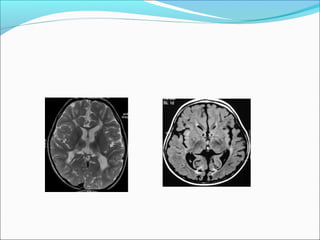

MRI Changes

hyperintense lesions in the IC and CR, with reduced

ADC values. B, Follow-up DWI obtained 4 days after

symptom improvement shows that the hyperintense

lesions have disappeared, with normalization of ADC

values.